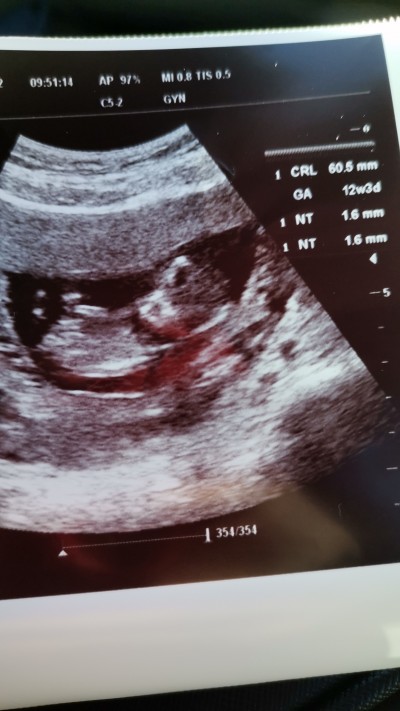

image

bbenim kine bak

Bana o zmanda doktor erkek demişti

ERKEK CANIM ♡♡♡